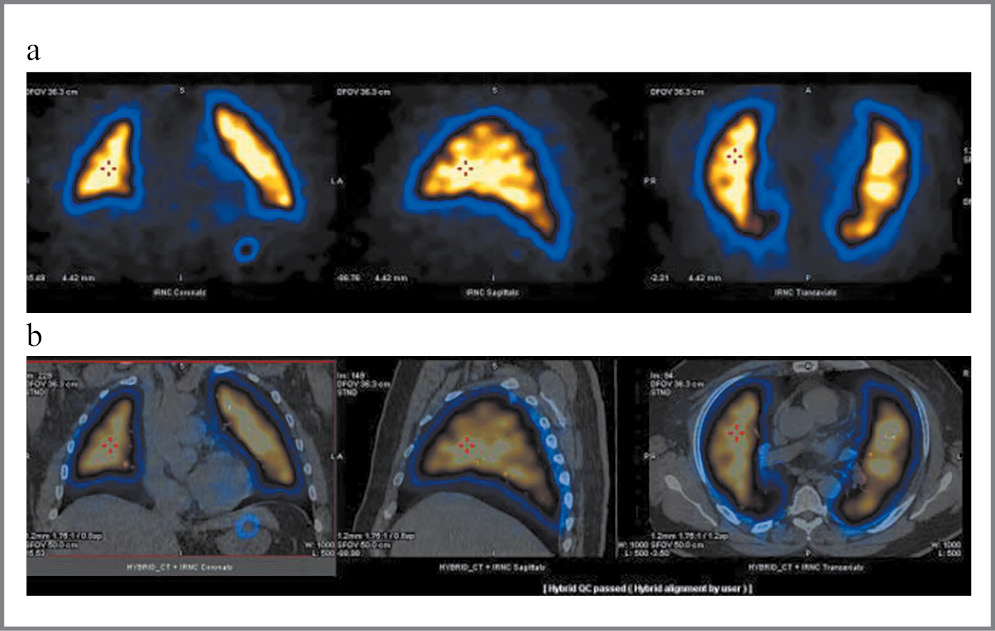

Оценка радионуклидных методов

Вентиляционно-перфузионная сцинтиграфия в режиме ОФЭКТ/КТ выполнялась только после выписки из стационара (рис. 8).

Рис. 8: а – ПС с 99mТс-макротехом в режиме ОФЭКТ; b – гибридное исследование: ПС с 99mТс-макротехом в режиме ОФЭКТ, совмещенная с КТ ОГК (фронтальная, сагиттальная, аксиальная реконструкции).

У 1 пациентки выявлен диффузно-очаговый дефицит перфузии, характерный для тромбоэмболии ЛА (ТЭЛА) с дефицитом 35%. У этой же пациентки еще на этапе стационарного лечения по поводу коронавирусной пневмонии по данным КТ ОГК с контрастированием диагностирована двусторонняя ТЭЛА.

У других пациентов данных в пользу очагового дефицита перфузии, характерного для ТЭЛА, не выявлено.

Но у большинства пациентов отмечался дефицит перфузии за счет диффузного снижения с явной тенденцией к уменьшению в более поздние сроки (табл. 4, рис. 9).

Что касается ВС, выявлена статистически достоверная разница между скоростью проникновения изотопа через альвеоло-капиллярную мембрану между двумя описанными группами пациентов.

При референсных значениях АКД в диапазоне от 55–108 мин у 1-й группы пациентов отмечалось ускорение проникновения изотопа (48,2±31,3 мин) через альвеоло-капиллярную мембрану, а у группы пациентов, обследованных в более поздние сроки, отмечалось замедление времени проникновения до 83,6±37,2 мин (см. табл. 4, рис. 10, 11).

Рис. 10. Оценка скорости АКД при ВС в ранние (30–60-й день) и поздние (61–180-й день) сроки после выписки.

Рис. 11: a – ВС с 99mТс-пентатехом в режиме ОФЭКТ; b – гибридное исследование: ВС с 99mТс-пентатехом в режиме ОФЭКТ, совмещенной с КТ ОГК (фронтальная, сагиттальная, аксиальная реконструкции).